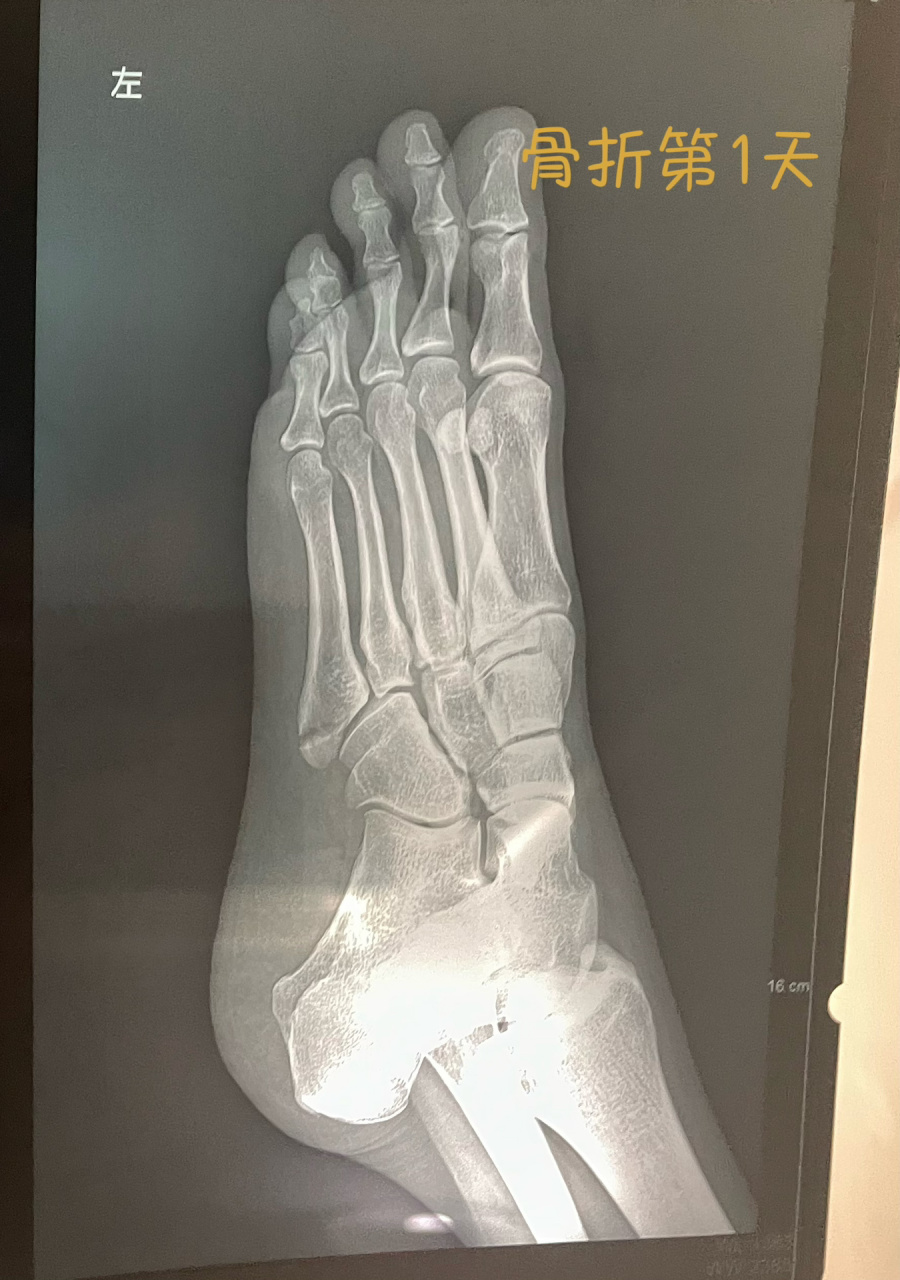

第五跖骨基底骨折62天

第五跖骨基底骨折4个月#没想到吧我也没想到 #骨折恢复记录 - 抖音